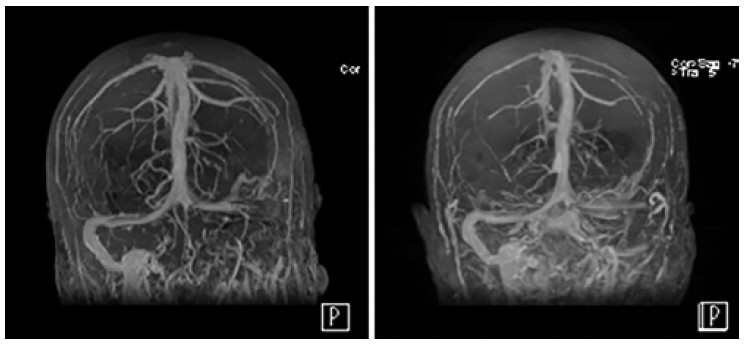

脑静脉窦血栓形成(CVST)是静脉窦区手术已知的重要并发症之一。尽管大多数CVST无症状,但重症CVST具有灾难性后果。本文作者通过前瞻性研究,评估术后CVST的发病率和相关危险因素。研究纳入74例经乙状窦后、经迷路或经枕下入路行后颅窝肿瘤切除或经幕上开颅行矢状窦旁肿瘤切除术的患者。所有患者术前、术后均行影像学检查以评估静脉窦的通畅性。74例患者中有24例(32.4%)术后MRV证实存在CVST,这些患者均无症状。统计学分析结果显示,包括年龄(p=0.352),BMI(p=0.454),性别(p=0.955),手术入路(p=0.909),手术时长(p=0.785),体液平衡(p=0.943),甘露醇使用(p=0.136),肿瘤类型(p=0.46,p=0.321)或肿瘤切除程度(p=0.253)与血栓形成均无明显相关性。除1名患者接受静脉输液治疗,其他患者均保守治疗。没有出现静脉梗塞,出血或神经功能障碍的病例。血栓形成组脑脊液漏发生率显著高于非血栓形成组(p=0.01)。作者指出,从影像学来看,术后CVST的发生率远高于之前回顾性研究所报道的发生率。对于未出现症状的CVST患者可以进行保守治疗。虽然未发现明确的危险因素,但术后脑脊液漏可能与CVST的发生关系密切。

图:术后颅内静脉窦血栓形成的MRV和保守治疗4个月后的MRV影像。